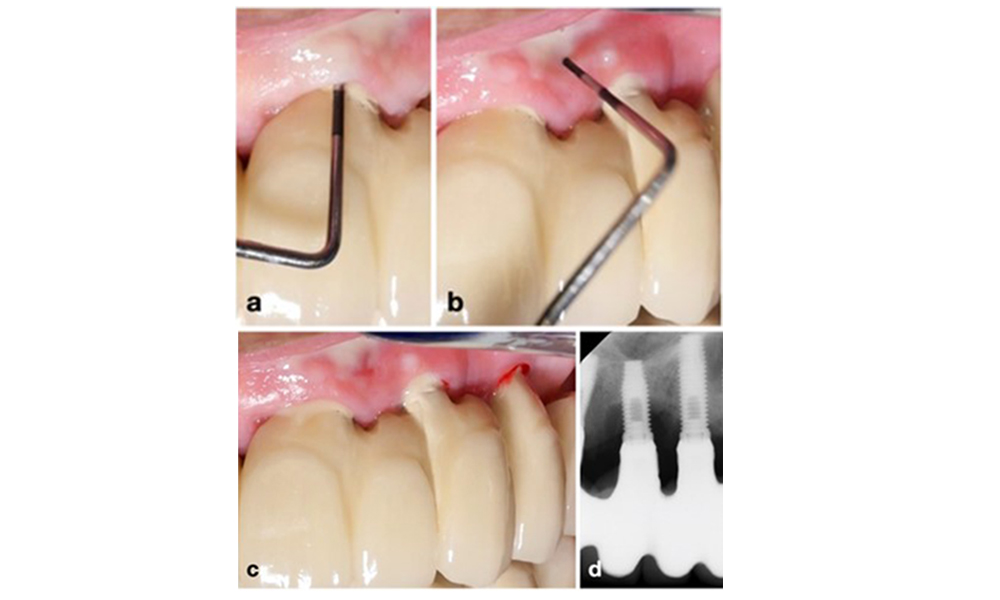

Auf dem World Workshop on the Classification of Periodontal and Peri‐Implant Diseases and Conditions 2017 wurden diagnostische Kriterien für periimplantäre Mukositis und Periimplantitis festgelegt (Renvert et al. 2018). Periimplantäre Mukositis ist definiert als (1) Entzündung um das Implantat (also Rötungen, Schwellungen, Blutfäden oder Blutstropfen innerhalb von 30 Sekunden nach dem Sondieren), jedoch (2) ohne zusätzlichen Knochenverlust nach der Ersteinheilung (Abb. 1).

Periimplantitis ist zu erkennen an (1) Entzündungszeichen, vergleichbar einer Mukositis, (2) einem radiologischen Nachweis von Knochenverlust nach Ersteinheilung und (3) der Zunahme der Sondierungstiefe im Vergleich zu Messungen kurz nach dem Einsetzen der prothetischen Rekonstruktion (Abb. 2). Liegen keine früheren Röntgenaufnahmen vor, weisen ein radiologisches Knochenniveau von ≥ 3 mm zusammen mit Sondierungsblutungen und Sondierungstiefen von ≥ 6 mm auf eine Periimplantitis hin.

Ein Knochenverlust von 1–2 mm gilt beispielsweise bei Implantaten auf Knochenniveau mit Außenverbindung allgemein als „normal“ (Abb. 2d, Implantat an Position 23).